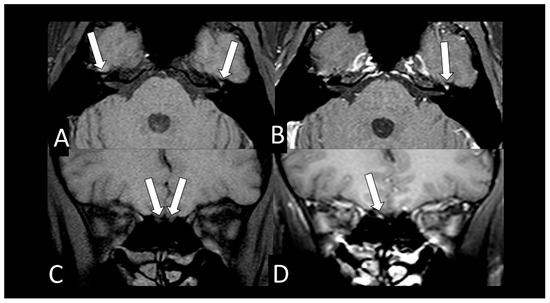

| 16 | F | 34 | yes | headache | yes | yes | no | no | olfactory bulb injury (MRI) | <25% | internal | no |

| 17 | F | 43 | no | headache, dizziness | no | yes | yes | no | olfactory bulb injury (MRI) | - | internal | no |

| 19 | F | 35 | yes | headache | yes | yes | no | no | olfactory bulb injury (MRI) | normal | internal | no |

| 24 | F | 25 | yes | headache | yes | no | no | no | olfactory bulb injury (MRI) | normal | external | no |

| 25 | F | 36 | - | headache | - | - | - | no | olfactory bulb injury (MRI) | normal | external | no |

| 28 | M | 80 | - | seizure, recurrent syncope | yes | yes | yes | O2 catheter | frontal microbleeding and olfactory bulb injury (MRI) | <25% | ICU | no |

| 32 | M | 40 | left facial palsy | yes | No | no | no | geniculate ganglion injury and olfactory bulb injury (MRI) | - | external | no | |